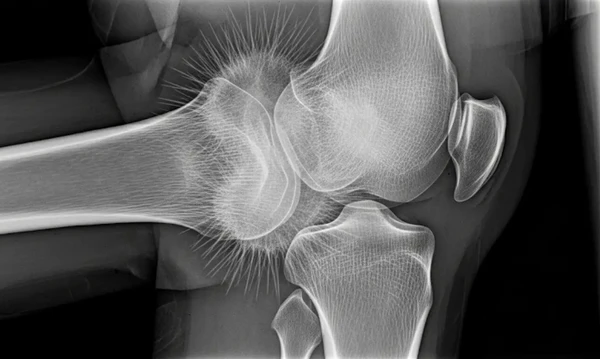

Geralmente, o tumor aparece nos ossos longos, como o fêmur, a tíbia, especialmente perto do joelho, e o úmero, próximo ao cotovelo. Cerca de 80% dos casos estão ligados ao fêmur.